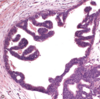

what is important to note about the papillary projections in papillary and micropapillary non-comedo ductal carcinoma in-situ

the projections lack fibrovascular cores

76

which two types of ductal carcinoma in-situ can produced nipple discharge

micropapillary and papillary